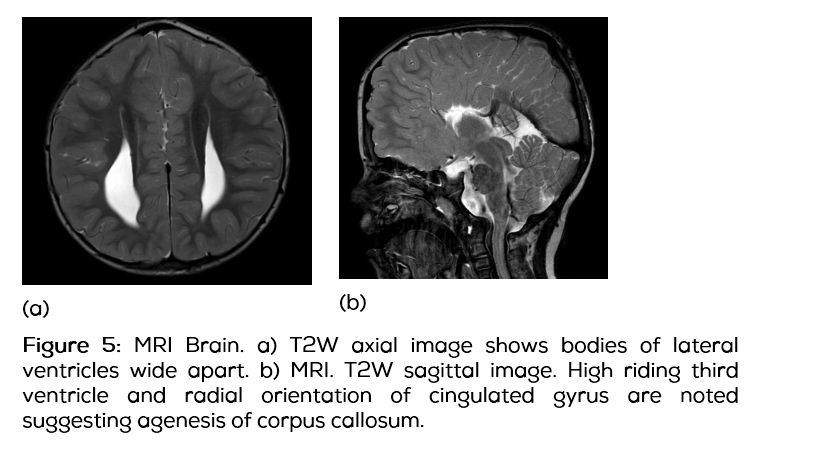

Further imaging with MRI revealed parallel bodies of lateral ventricles and pointed and pinched out frontal horns. Complete agenesis of corpus callosum with radial orientation of cingulate gyri and a high riding third ventricle were noted (Figure 5). Prominent temporal horns of both lateral ventricles and Probst bundles bilaterally and vertical orientation of hippocampi were seen.

Apert syndrome has distinctive clinical features. The coronal suture fuses prematurely (at less than 3 months), leading to an acrocephalic (cone-shaped) head with shortened antero-posterior diameter, and a high prominent forehead [8-11]. In our case, in addition to the coronal suture, the sagittal, lambdoid and metopic sutures were also fused. This is a unique feature in our case, as it has not been reported previously. Brachycephaly, hypertelorism, midface hypoplasia occurs. There is prominence of the mandible with resultant malocclusion. These features were present in our case. A high arched palate and cleft palate (30%) is a feature [1]. Our case had a high arched palate, however there was no associated cleft. The digital manifestations include distal (acro-) fusion (syndactyly) of commonly the second to fourth digits of the hands. These findings are frequently symmetrical. The thumb may be incorporated into the mid-hand syndactyly as seen in our patient. Progressive longitudinal fusions also occur (symphalangism). Fusion of bodies of C5 and C6 are seen in our patient, a common feature noted in 70% of the cases [1]. There are associated cardiac and genitourinary abnormalities in 10% of patients. Ventriculomegaly and abnormalities of the corpus callosum and septum pellucidum are not uncommon. Examination did not reveal any cardiac or genitourinary abnormalities. MRI showed ventriculomegaly with agenesis of corpus callosum, absent septum pellucidum, vertical hippocampi and a high riding third ventricle. Previous studies reported affected individuals with anomalies of viscera, elbows and shoulders, skeleton and central nervous system with impaired mental function [10, 12]. There were no anomalies of the viscera, elbows or shoulders.